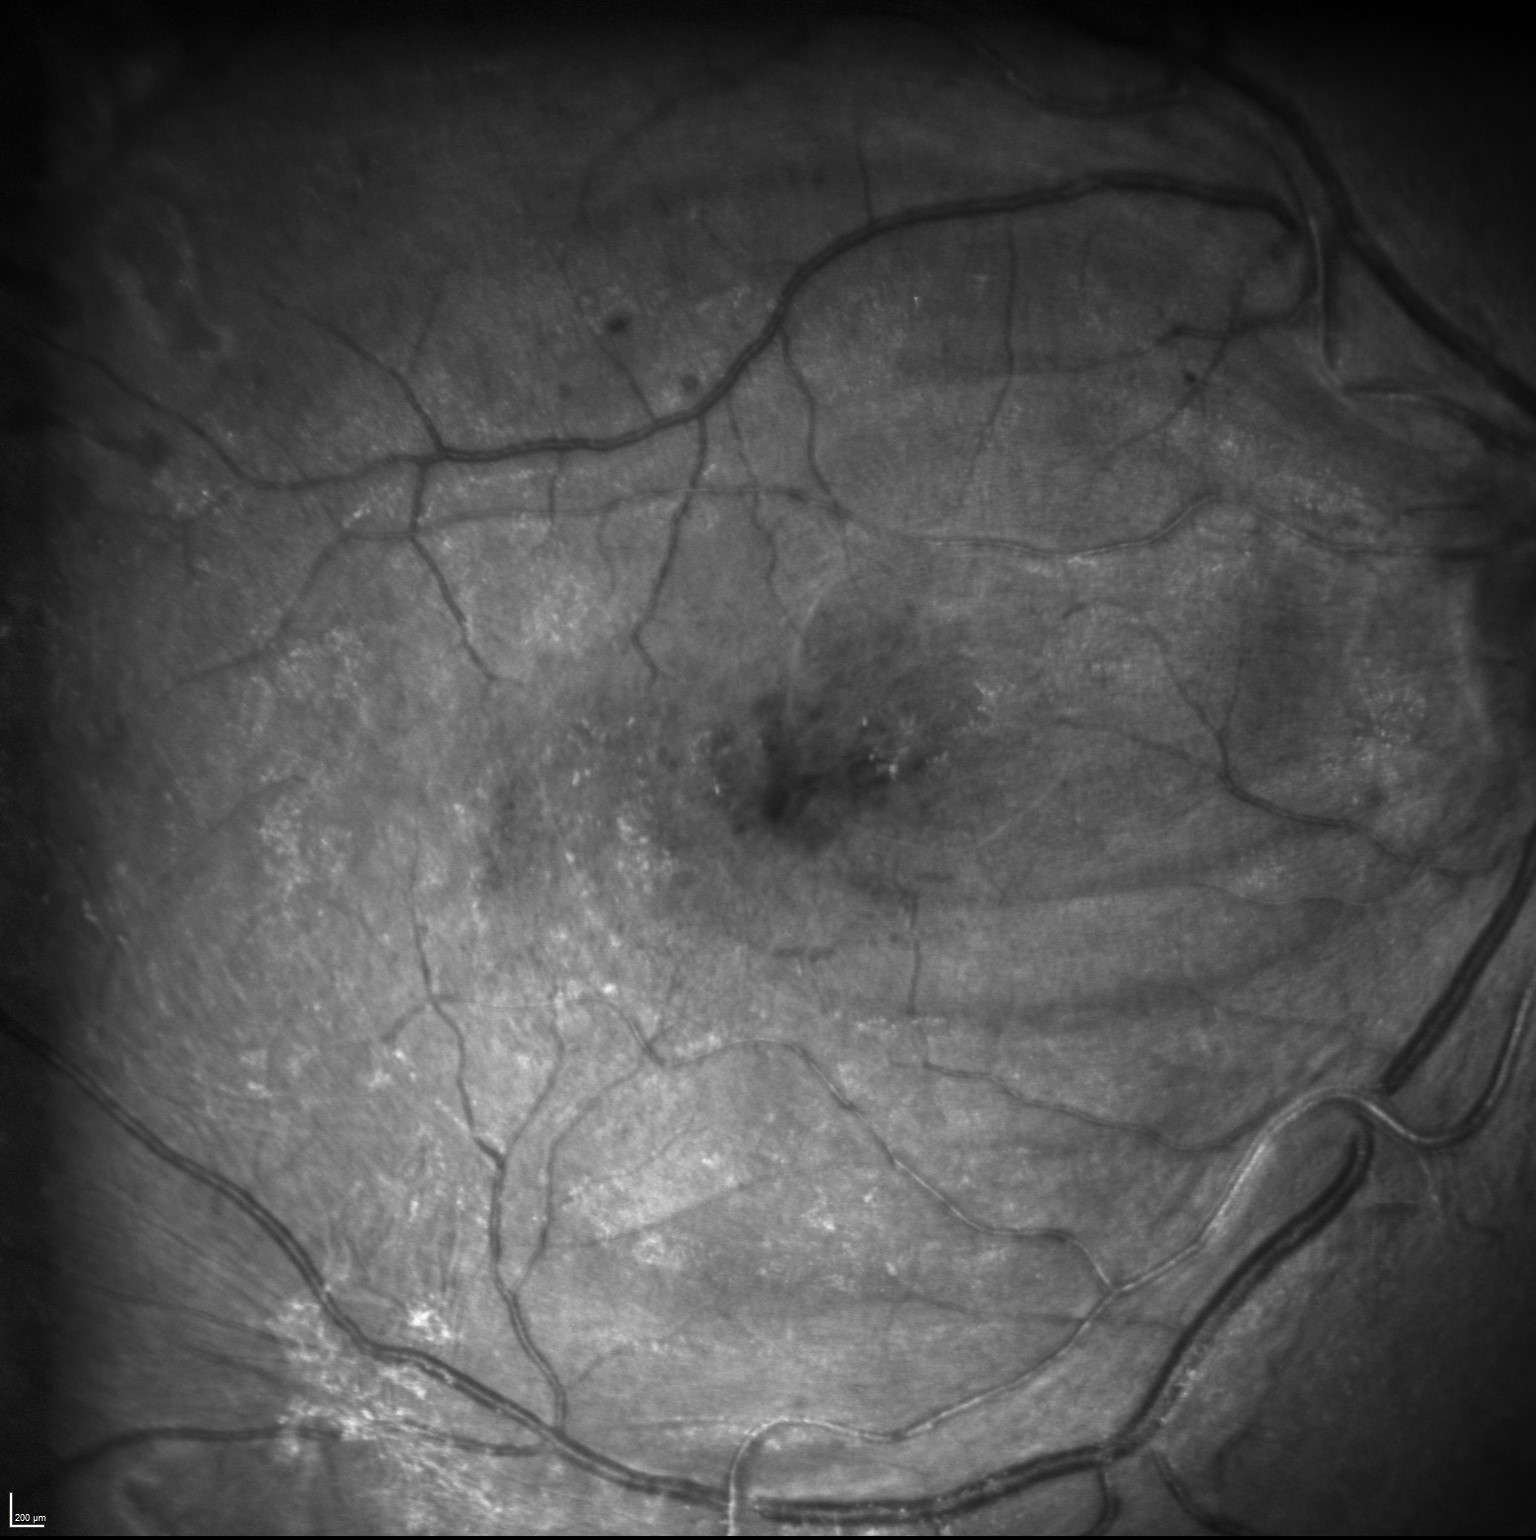

Reflectancia